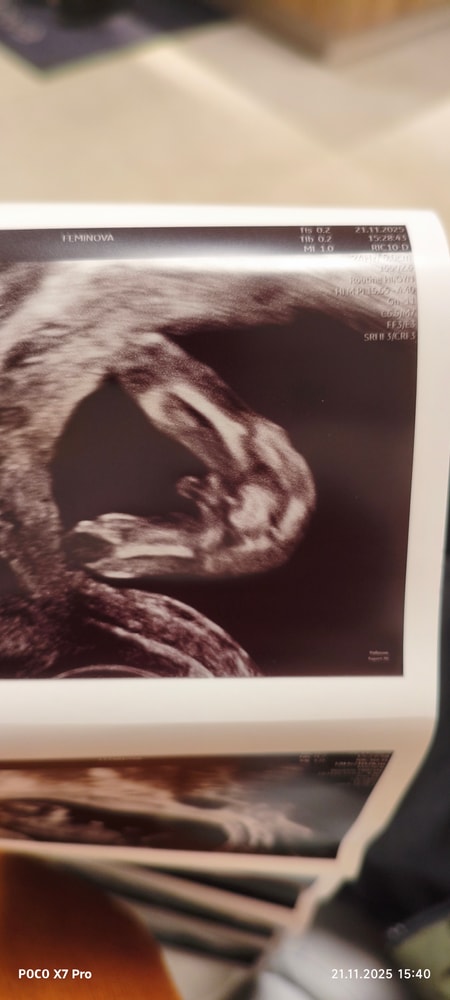

Там уже далеко не под вопросом🤣 там ого-го какой мальчик 😅

Была бы девочка - ничего бы не сказали )) Меня с дочерью мурыжили - типа ниче не видно, наверное, девочка. А сына в 12 недель рассмотрели. Но 100% не обещали, конечно. Но все было очевидно.

Вообще на таком сроке снизу не смотрят, но мне именно снизу предположили верно младшего сына. Потому, действительно похоже на мальчика. Но это пока только предположительно, конечно.